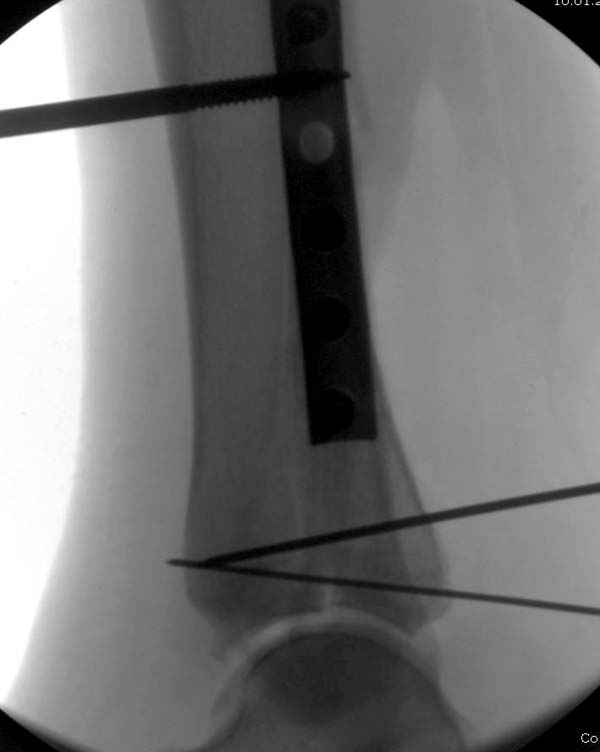

По снимкам довольно сохранный сустав, и такой сустав желательно попытаться восстановить всеми возможными мерами.

Насчет пилона, прошло достаточное время для консолидации и прекрасная возможность для демонстрации, что такие случаи могут быть успешно вылечены остеотомией, несмотря на засторелость.

Из заднего доступа остеотомия тонким остеотомом и коррекции на ЭОПе.

Без применения сложной конструкции, а обычными параллельными шурупами. Шурупы в 3.5 мм и дополнительно фиксация крючковидной пластиной, сделанной из 3.5 mm semitubular пластиной, Butress или аntiglade фиксация.

Здесь алгоритм фиксации свежего перелома и преоперационный план для обсуждаемого случая.